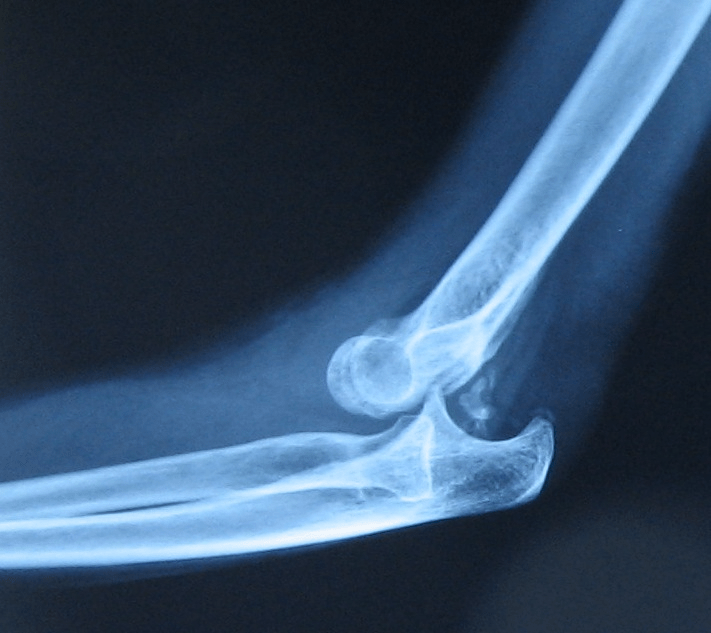

The Ligament Damaged in this Image. (OK for Abbr...but must be able to say what it stands for)

MCL (Medial Collateral Ligament)